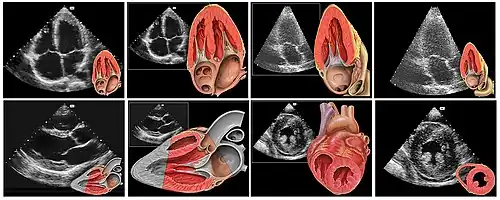

Le cœur est un organe intra thoracique, entouré d'air (les poumons) et d'os (les côtes). Ces deux dernières structures ne laissent pas transmettre les ultrasons, rendant l'examen plus complexe. On se sert ainsi d'un nombre limité de « fenêtres » anatomiques, lieux où le cœur peut être visualisé par l'échocardiographie, sans interposition aérienne ou osseuse.

Le patient est installé torse nu, allongé sur le côté gauche (décubitus latéral gauche). Il n'a pas besoin d'être à jeun. Éventuellement, trois électrodes sont collées afin de disposer d'un tracé ECG simultané. L'examinateur, suivant son habitude, est à la droite ou la gauche du patient. Il applique la sonde d'échographie recouverte d'un gel (permettant un meilleur passage des ultrasons à travers la peau) sur la peau de ce dernier suivant différentes positions constituant les fenètres d'échographie dont les principales sont :

- « Voie para sternale gauche » : entre la troisième et la quatrième (voire entre la quatrième et la cinquième) côte, juste à gauche du sternum ;

- « Voie apicale », partie inférieure gauche du sternum, là où est perçu le mieux à la palpation le battement cardiaque (« choc de pointe ») ;

- « Voie sous costale ou sous xyphoïdienne », dans le creux en dessous de la xiphoïde du sternum.

Échographie tridimensionnelle

Par le biais d'un capteur non plus linéaire, mais matriciel, une imagerie tridimensionnelle directe est possible. Cette technique relativement nouvelle (la sonde matricielle étant disponible à relativement grande échelle depuis 2002), est en cours d'évaluation.